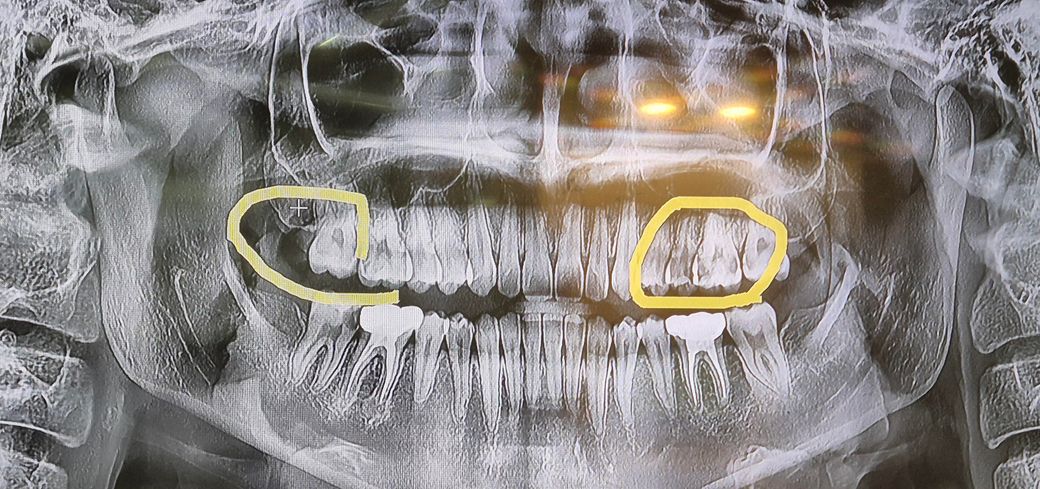

심한치통으로 치료를하러 갔는데 아픈치아 외에 저 동그라미 친 다른치아도 충치가 심해서 신경치료해야된다고 했습니다. 몇년전부터 단것만 먹으면 모든 어금니가 다 아팠는데 양치를 열심히 한뒤로 최근1년간은 단것먹어도 치통이 없어서 충치가 사라진줄 알았습니다. 저 동그라미 친부분도 충치가 심한치아라 신경 치료를 해야되는 상황인가요

?

네 엑스레이상에서 동그라미 쳐진 치아 3개에 사진상 왼쪽 아래 맨뒤 어금니 다 충치보이고 꽤 깊어 신경치료 가능성이 있는 경우로 보입니다